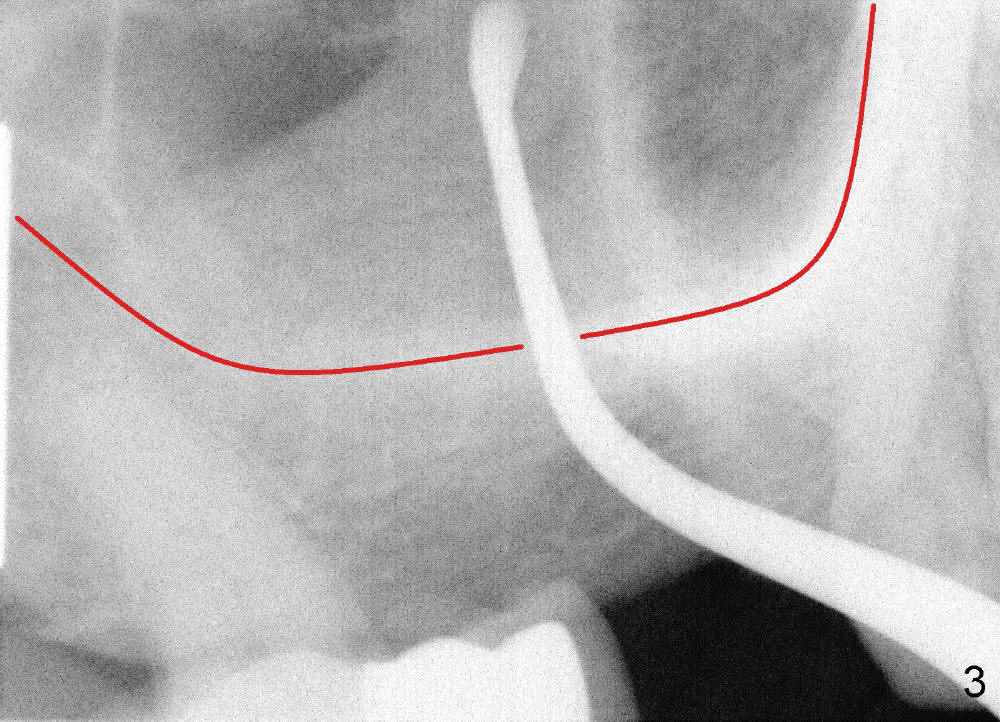

Lack of bony support and soft tissue coverage appear to be an obstacle to immediate implant. Two cases are presented. The first one is my first attempted immediate implant patient (Fig.1-3), a 54-year-old lady. She is extremely apprehensive. The upper right first molar has severe perio-endo disease. There is no bone around the buccal roots (MB, DB in Fig.1). The tooth is non salvageable and is treated the best with an immediate implant. When the tooth is extracted, the large buccal gingival defects (Fig.2 MB, DB) and sinus perforation (Fig.3) through the palatal socket (Fig.2 *) are apparent contraindications to immediate implant. Amazingly, the gingiva heals rapidly post extraction. An implant is placed 1 month later.